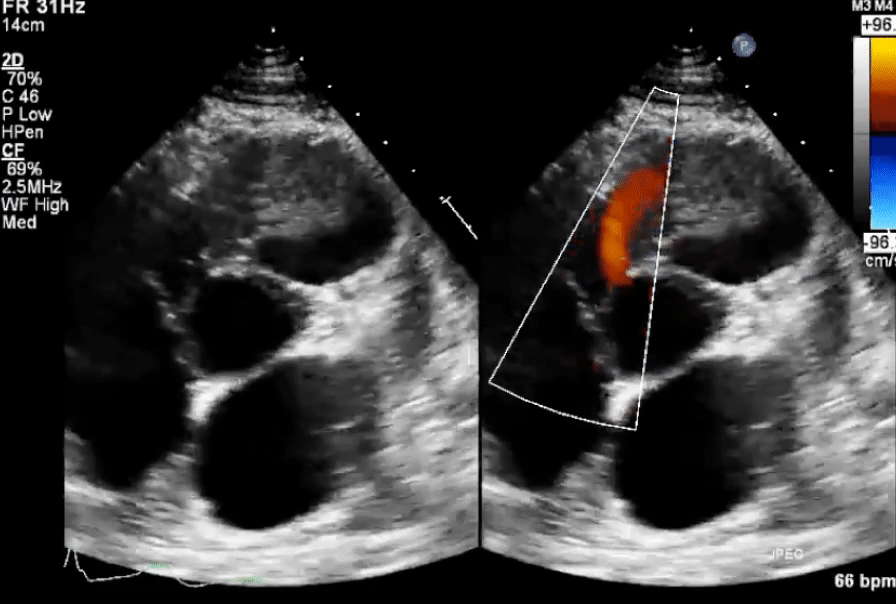

Echo in VSD

-1754871370645.webp)